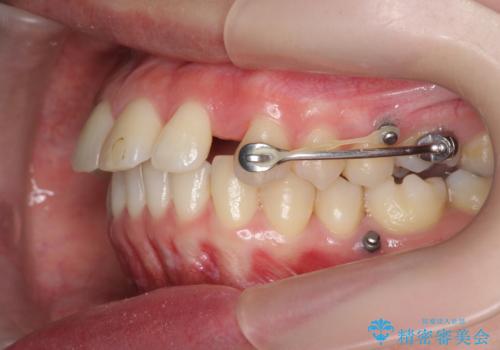

カリエール・マイクロインプラントを併用した歯の突出を改善する大きな遠心移動

カリエール・マイクロインプラントを用い、時間はかかりましたが大きく歯の後方移動が達成され、前歯の見た目が大きく改善されました。

大きな後方移動を達成するにはマイクロインプラントと日常的なゴムかけが大切です。